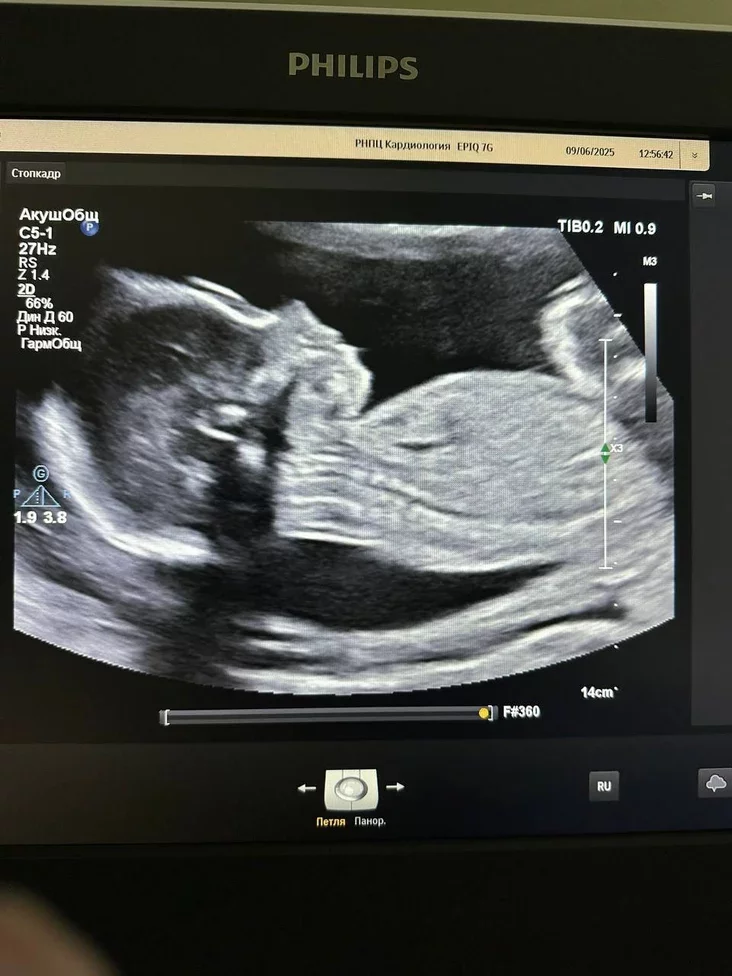

Как пояснили в ведомстве, это была первая такая операция в истории белорусской медицины. В июне 2025 года, когда ребенку было всего 23 недели от зачатия, врачи обнаружили в левом предсердии миксому — доброкачественную опухоль, которая могла вызвать тромбоэмболию, инсульт или инфаркт и угрожала жизни и матери, и ребенка.

Чтобы удалить образование, специалисты провели сложную операцию на открытом сердце с использованием искусственного кровообращения. Благодаря слаженной работе команды из РНПЦ «Кардиология» и РНПЦ «Мать и дитя» на 23‑й неделе беременности угрожающую ситуацию удалось успешно разрешить. Операцию проводил кардиохирург Евгений Костюкович.